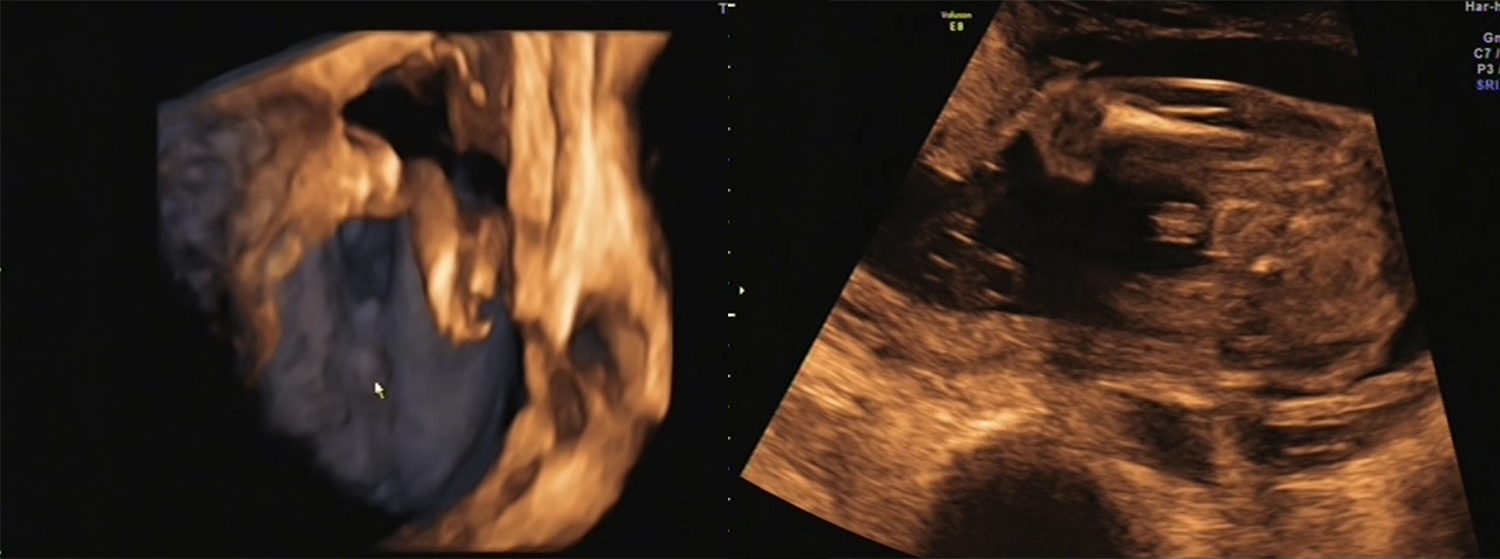

Attachment 10335BOY!!!!

Although, after two girls, we're a little skeptical so I've attached the pics from today anyway for you to see.

I'm thinking it's rather obvious but the sonographer wouldn't give me the 100%. ;) Here's hoping!